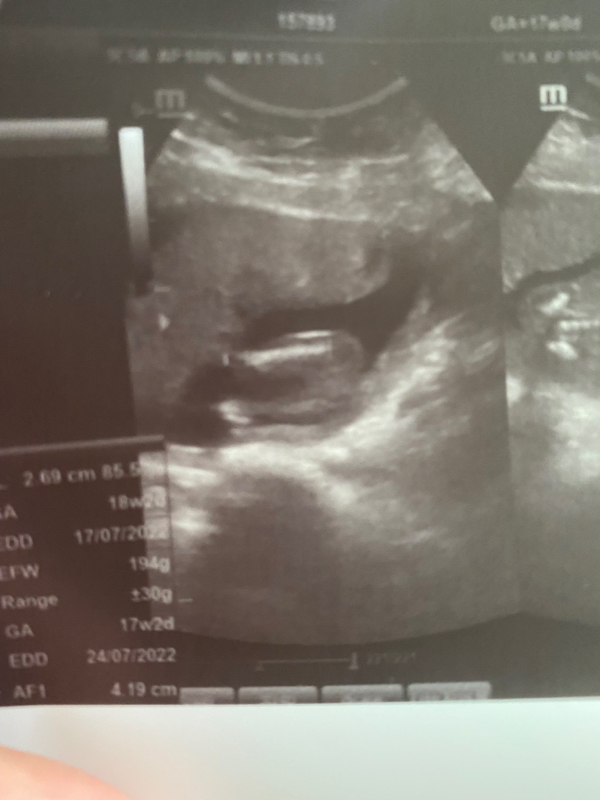

بنات انا هذا السونار حقي قبل اسبوعين قالت مو واضح لكن احساسي انه بنت يعني ما احس اشوف شي بس الجهاز حقها مغبش وردئ لكن شوفو لي وش رايكم بنت ولا ولد